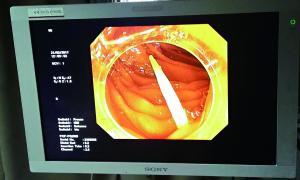

卡在腸道中的牙簽的影像檢查圖。

據(jù)中山一院胃腸外科譚進富副主任醫(yī)師介紹,胃鏡檢查發(fā)現(xiàn),這根牙簽一路下滑,滯留在小腸,一端刺破腸道,鉆出去的部分占了三分之二長,引發(fā)了嚴重感染。